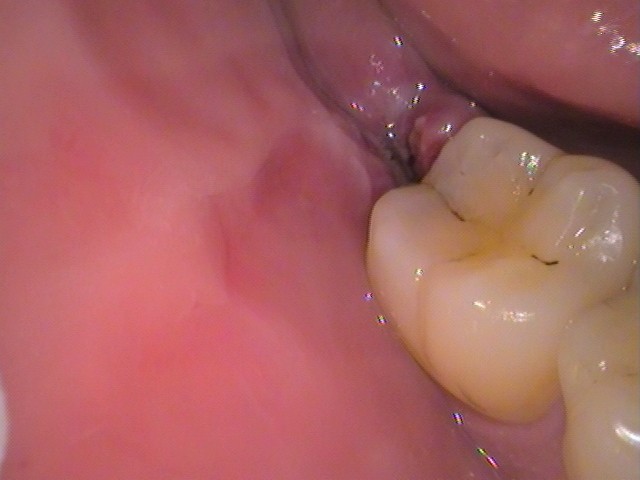

お口の中を見てみると、

このような状態。

親知らずがひょっこり顔を出しているのが分かりますね。

ここです。